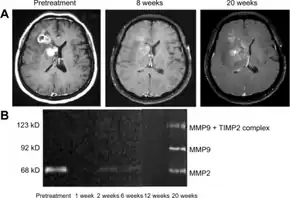

Recurrent glioblastoma, MRI during bevacizumab monotherapy a) Pretreatment, 8 weeks after treatment, and 20 weeks after treatment b) MMP activities in urine

Bevacizumab slows tumor growth but does not affect overall survival in people with glioblastoma multiforme.[25] The FDA granted accelerated approval for the treatment of recurrent glioblastoma multiforme in May 2009.[26][27] A 2018 Cochrane review deemed there to not be good evidence for its use in recurrences either.[25]